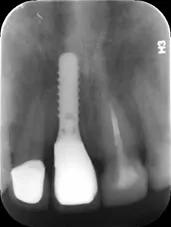

3.种植牙

与活动假牙、烤瓷牙牺牲周围牙齿保全自己的做法相比,种植牙是能和真牙打成一片的。

种植牙是将种植体(金属钛,可与人体结合)放入缺牙区的牙槽骨充当人工牙根,不依靠邻牙就能站稳脚跟。

种植牙形态美观、舒适、固位稳定,功能与天然牙近似,能高效地行使咀嚼功能,且无需磨损旁边的牙齿,对邻牙没有任何伤害。

无需活动牙类似的卡环或基托,没有异物感,寿命长,只要不是遇人不淑没种好,种上的牙齿至少能用30余年。

而且种植手术是一个较小的手术,类似拔牙手术,采用局部麻醉,手术只需要半小时左右即可完成,创伤小,术后2小时即可进食。缺点是种植牙的成本比较高、对口腔医生的技术要求也较高,治疗费用相对比较高。